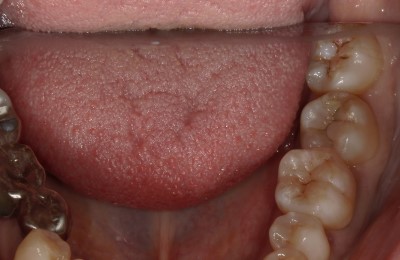

CASE03ダイレクトボンディング

Before

-

After

| 主訴 | できるだけ歯を削らずに銀歯を白くしたい。 |

|---|---|

| 治療方法 | 銀歯を除去した後、ダイレクトボンディング法によりコンポジットレジンを用いて修復した。 |

| 治療期間 | 1回 |

| リスク | 長年使用することによる着色。咬合圧が強い場合破折することがある。 |

| 費用 | 55,000円×2(税込み) |